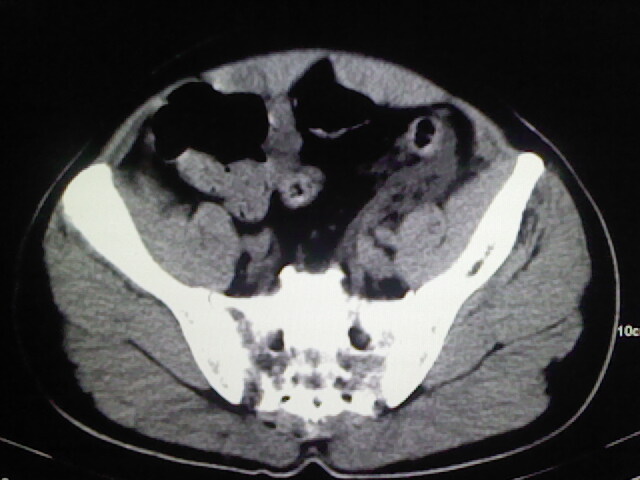

以下是引用zsl6918在2009-2-7 7:29:00的发言:[br]请提供介入的方式方法,肾及输尿管改变考虑与介入损伤有关,漏了,尿液外渗。

以下是引用余辉在2009-2-7 8:27:00的发言:[br]可能是硬化剂烧穿囊壁进入肾盂输尿管了,尿漏。不除外介入或碎石术后合并感染[br]患者术后怀疑结石,接着就碎石了?就怀疑没有确诊吗?碎石用的什么方法?气压弹道还是体外超声?如果这样的话责任人都难找

以下是引用随光逐影在2009-2-7 8:46:00的发言:[br]支持3楼意见。[br]另:不排除左肾及肾周感染可能。